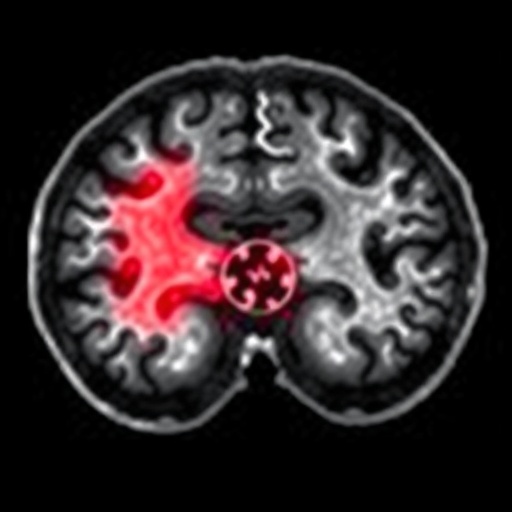

Intracerebral hemorrhage, a devastating subtype of stroke characterized by bleeding within the brain tissue, demands immediate diagnosis and intervention. Current diagnostic modalities heavily rely on neuroimaging techniques such as computed tomography (CT) scans, which are accessible primarily within hospital environments. Delays inherent to patient transportation and imaging acquisition can exacerbate brain damage, reduce treatment efficacy, and worsen prognoses. Enter the emerging frontier of circulating biomarkers, particularly extracellular vesicles, as non-invasive harbingers of pathological states within the central nervous system.

The core of this breakthrough rests on exploiting steric exclusion effects generated by membrane pore geometry and surface chemistry. As biofluid samples, such as blood plasma acquired via finger prick, flow through the microfluidic device, larger vesicles are selectively hindered from passing through nanopores of precise dimensions, while smaller vesicles traverse unimpeded. This enables real-time enrichment and segregation of EV subsets associated with hemorrhagic brain injury, which exhibit characteristically distinct size distributions.